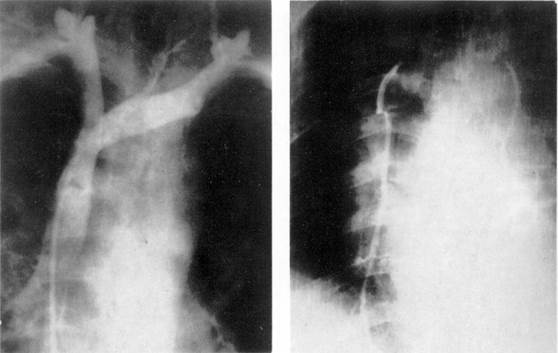

Рис. 7. Селективная ангиография бронхиальных артерий.

При селективной ангиографии бронхиальных артерий катетер вводится в грудную аорту и далее — до устья бронхиальных сосудов; введение контрастного вещества осуществляется с помощью автоматического инъектора. Сериография, проводимая, как правило, в переднезадней проекции, может быть дополнена рентгенограммами в боковой или косой проекциях в зависимости от задач исследования (рис. 7).

При анализе бронхиальных ангиограмм определяются уровень и тип анатомического ветвления сосудов, положение, форма, диаметр, характер контуров сосуда, извитость его и проходимость, характер и уровень окклюзии, степень развития коллатеральных ветвлений и их взаимосвязь с легочной артерией. Учитываются уровни анастомозирования двух систем кровообращения легких (субсегменты, сегменты, доли или

![]() |

лобулярные ветви легочной артерии).